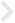

인공수정체의 위치 이상(인공수정체 탈구)

백내장 수술시 삽입했던 인공수정체가 정상 위치를 벗아난 경우를 말하며, 이탈된 정도에 따라 앞이 뿌옇게 보이고, 시력저하가 나타납니다.

카나브라바 고정술

수술 전

수술 후